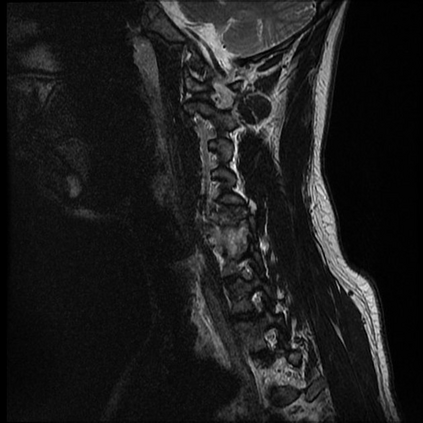

In this study, we aim to initiate the development of Radiology Foundation Model, termed as RadFM.We consider the construction of foundational models from the perspectives of data, model design, and evaluation thoroughly. Our contribution can be concluded as follows: (i), we construct a large-scale Medical Multi-modal Dataset, MedMD, consisting of 16M 2D and 3D medical scans. To the best of our knowledge, this is the first multi-modal dataset containing 3D medical scans. (ii), We propose an architecture that enables visually conditioned generative pre-training, allowing for the integration of text input interleaved with 2D or 3D medical scans to generate response for diverse radiologic tasks. The model was initially pre-trained on MedMD and subsequently domain-specific fine-tuned on RadMD, a radiologic cleaned version of MedMD, containing 3M radiologic visual-language pairs. (iii), we propose a new evaluation benchmark that comprises five tasks, aiming to comprehensively assess the capability of foundation models in handling practical clinical problems. Our experimental results confirm that RadFM significantly outperforms existing multi-modal foundation models. The codes, data, and model checkpoint will all be made publicly available to promote further research and development in the field.